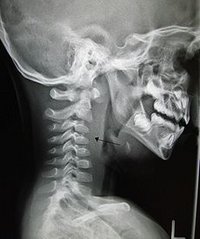

CT is the definitive diagnostic test. [4]

X ray of the neck 80% of the time shows swelling of the retropharyngeal space. If the retropharyngeal space is more than half of the size of the C2 vertebra, it may indicate retropharyngeal abscess.[5]